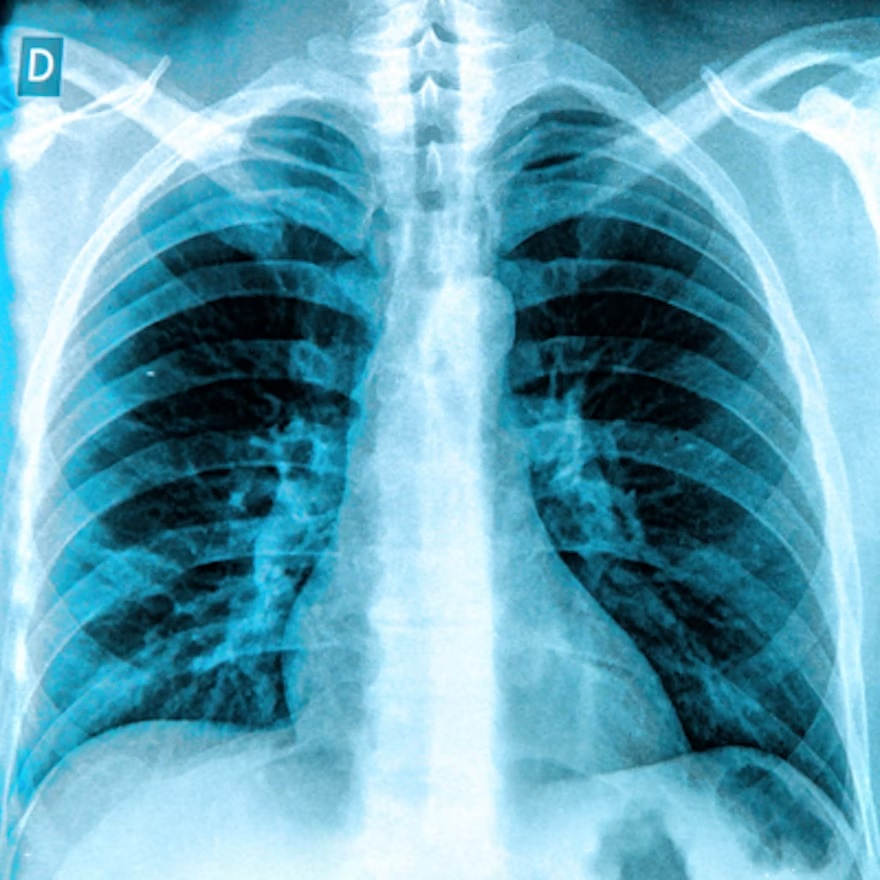

Rad-Aid International investigators have described a successful strategy for deploying chest x-ray AI to help diagnose tuberculosis in low- and middle-income countries, according to a recent study in the Journal of the American College of Radiology.

Specifically, in Guyana, it revealed an 87% concordance rate between radiologists and the AI model for triaging normal versus abnormal chest x-rays. In Nigeria, the researchers noted an 85% concordance rate between radiologists and the AI model for reporting tuberculosis on chest x-rays.